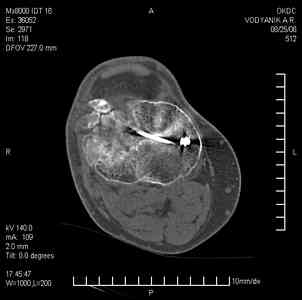

Тугой ложный сустав правого бедра в сочетании неправильно сросшимся переломом большеберцовой кости |

Уважаемые коллеги,В ортопедическое отделение обратился пациент: мужчина 47 лет, который в течение 4-х лет дваждыполучил травму костей, образующих правый коленный сустав. В 2002 v внутрисуставной оскольчатыйперелом проксимального метаэпифиза правой большеберцовой кости; в 2005 v внутрисуставнойоскольчатый перелом дистального метаэпифиза правой бедренной кости. В обоих случаях в разных лечебных учреждениях проводилось оперативное лечение переломов.При осмотре в отделении на основании результатов клинического осмотра и данных визуальныхметодов обследования поставлен диагноз:тугой ложный сустав дистальной трети правой бедренной кости, состояние после накостногоостеосинтеза перелома типа 33-В2.2 ; несросшийся перелом надколенника; неправильно сросшийсяперелом латерального мыщелка правой большеберцовой кости, состояние после металлоостеосинтезаперелома 41-В2.2; сочетанная осевая деформация правой ноги: варусная деформация правого бедра,вальгусная деформация правой голени; посттравматический артроз коленного сустава 4 ст по Kellgren-Lowrence; выраженное нарушение функции ходьбы и опоры. Внешний вид ноги больного, данные рентгенографического обследования и избирательно выделенные компьютерные томограммы приведены в приложении. В именах КТ использовано кодирование уровня по АО, т.е. _41, например, означает проксимальную треть голени.В отделении намечен v очень предварительно v следующий план лечения: 1. Иметь ввиду перспективу тотального эндопротезирования коленного сустава. 2. С учетом п.1 при проведении действий, направленных на устранение ложного сустава бедренной кости не использовать материалы, не подвергающиеся трансформации. 3. В ходе операции, направленной на устранение ложного сустава: А. удалить все металлоконструкции; Б. ревизовать зону пролежня под пластиной на бедре, при наличии признаков достаточной жизнеспособности кости выполнить остеопериостальную декортикацию, дрилинг ложа пластины; В. Удалить рубцовую ткань по плоскости ложного сустава, и в пространстве между костными форагментами, насечь обращенные друг к другу поверхности. Ввести штифт с блокированием (например Stryker с учетом особенностей расположения дистальных блокирующих винтов у этойконструкции). Осуществить остеосинтез с учтанением варусной деформации бедренной кости. Пространство в зоне ложного сустава и пустоты в метафизе бедренной кости заполнить резорбирующимся цементом на основе гидроксиапатита кальция. Для дистальной фиксации использовать винты с переменным шагом резьбы. Вариант:, винты вводить после заполнения метафиза цементом. Дополнительные виды создания межфрагментарной компрессии во встречно-боковом направлении обсуждаются. Г. Быть готовым к кровопотере. Д. Учесть высокий риск инфекции, тромбоэмболических осложнений. Е. Вопрос о внешней иммобилизации решить по результатам оценки стабильности остеосинтеза. Вариант - одноосевой стержневой аппарат для шунтирования гвоздя с модулем на голени и дистракцией коленного сустава в течение 3-5 недель. Просим вашей критики намеченного плана и конструктивных предложений. С уважением к сообществу, Ординатор В.С. Саплин

Движения приличные, есть за что бороться. Такая ротация голени кнаружи, если она действительно есть (для уточнения можно сделать КТ на уровне обоих метафизов и бедреных, и берцовых ксотей, не меняя положение ног во время съемки), большого значения не имеет. А уж на фоне всего остального тут - вообще говорить не о чем.